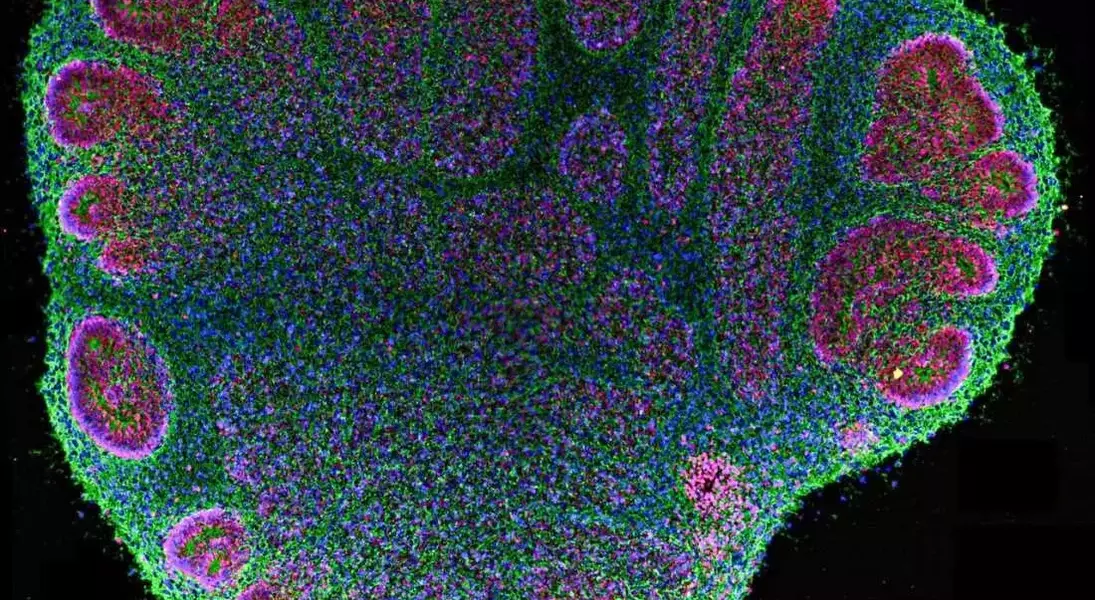

Significant strides are being made in neurological research through the utilization of human brain organoids, which are aggregates of brain cells. These microscopic neural structures are instrumental in studying the intricate development of the human brain and modeling various conditions such as autism, schizophrenia, and even aggressive brain cancers. Scientists are now able to cultivate these organoids for extended periods, observing their growth and interaction, thereby gaining unprecedented insights into brain function and dysfunction.